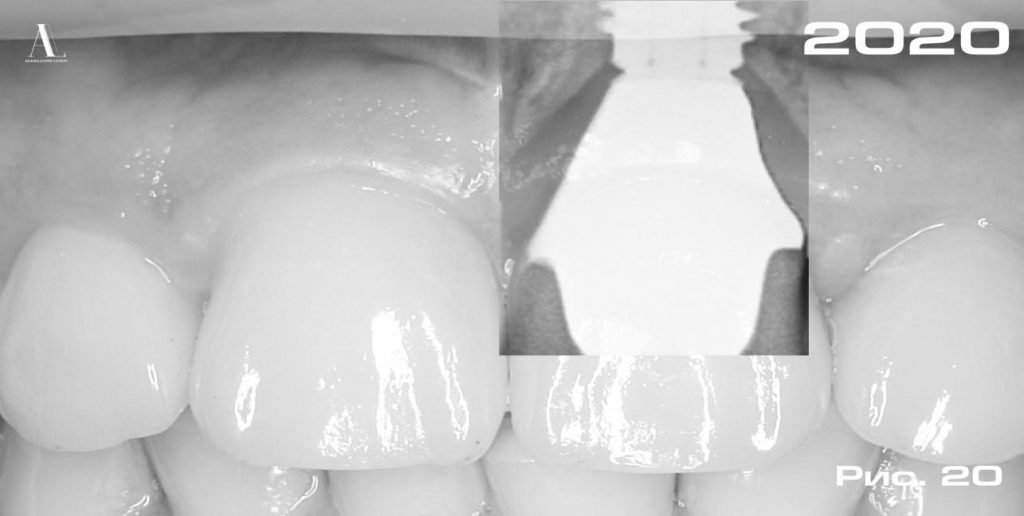

В данном клиническом случае удалось добиться не только высоко-эстетичного, но и стабильного результата лечения, о чем свидетельствует отсутствие резорбции костной ткани в области платформы дентального имплантата через 3 года после имплантации (Рис. 20).